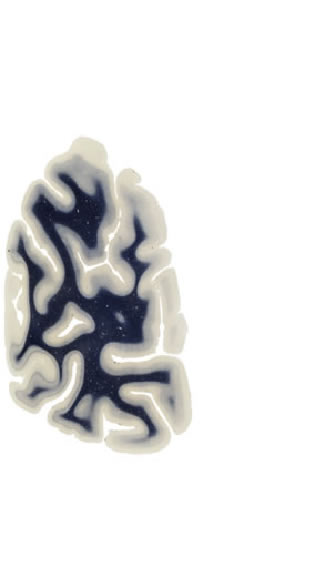

Hi-Resolution Sections · Cells (Nissl Staining) · Virtual Microscopy

Frontal sections (Nissl) from the Atlas Brain:

Slice ID:

r5-0450

Plate NR:

66-67

Position:

88,8 mm